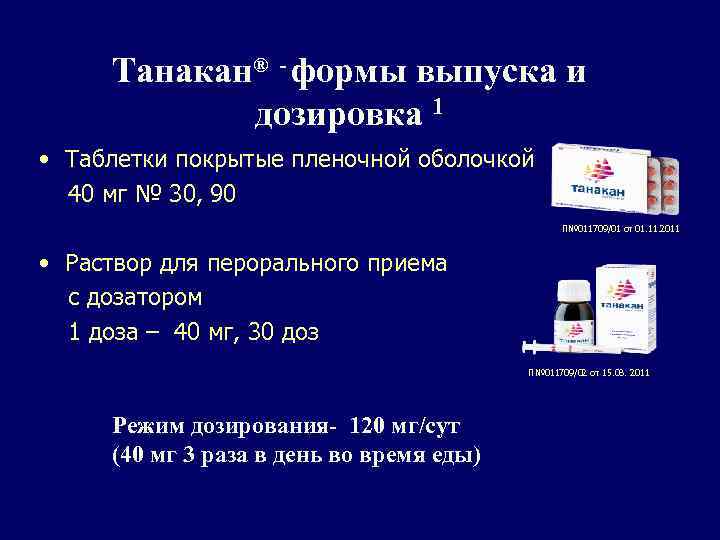

Танакан® - формы выпуска и дозировка 1 • Таблетки покрытые пленочной оболочкой 40 мг № 30, 90 П№ 011709/01 от 01. 11. 2011 • Раствор для перорального приема с дозатором 1 доза – 40 мг, 30 доз П№ 011709/02 от 15. 08. 2011 Режим дозирования- 120 мг/сут (40 мг 3 раза в день во время еды)